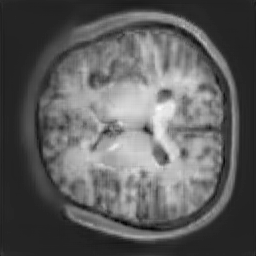

The study utilizes three 3D datasets, namely the GSP dataset[3], the LIDC-IDRI dataset[1], and the dataset employed for the Lung Nodule Analysis 2016 (LUNA16) challenge[21] which is a subset of LIDC-IDRI dataset. Samples from generated images at different stages of training are presented in Fig. 2 and Fig.3.

Figure 2: Synthetic images of CRF-GAN and HA-GAN at different iterations of training on GSP dataset